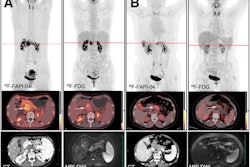

The group enrolled 69 adults with EHH from five centers in the Netherlands and France. All participants underwent Ga-68 NODAGA-exendin-4 (exendin) PET/CT and at least DOTA-SSA PET/CT and triple-phase contrast-enhanced CT (CECT) or CE- diffusion-weighted imaging-MRI (DWI) MRI. Endoscopic ultrasound (EUS) was performed in a subgroup of patients when noninvasive imaging was inconclusive.

Based on clinical readings by experts, the accuracy of exendin PET/CT was higher than any other technique, according to the findings. CECT found lesions suspicious for insulinoma in 63% of patients; CE-DWI-MRI identified lesions in 60% of patients; CECT and CE-DWI-MRI combined in 68% of patients; DOTA-SSA PET/CT in 55% of patients; EUS in 71% of patients; and exendin PET/CT in 79% of patients.

“This study demonstrates the superiority of exendin PET/CT in a unique prospective comparison to all current routine imaging modalities for preoperative localization of benign insulinomas,” the group wrote.